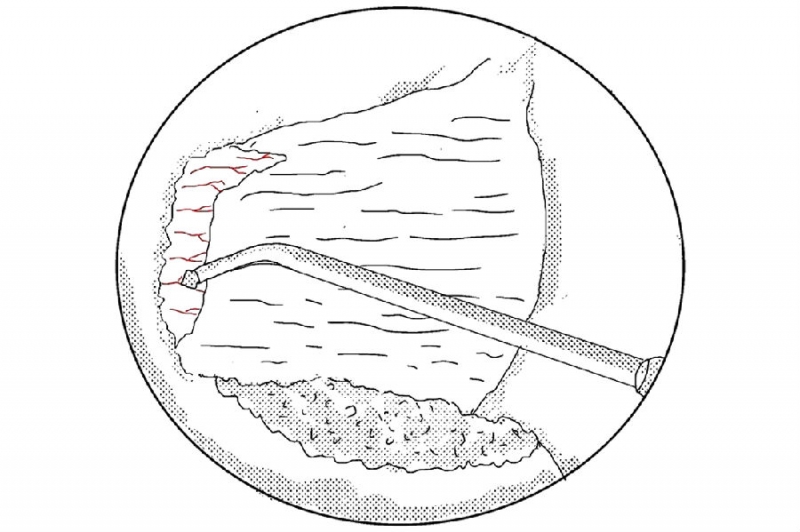

5. 使用小的射频刀头在止点区域进行止血;

6. 使用骨凿将磨薄的下关节内缘凿除显露Corner和上关节突内缘;

7. 使用反向的椎板咬骨钳减压同侧Corner部位;

8. 减压的外界参考椎弓根内壁;

9. 切除椎弓根内缘同时松解黄韧带外缘;